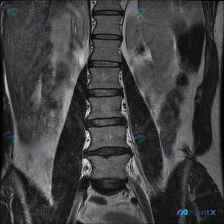

整理到一份腰椎MRI-T1序列-冠状位的影像资料,有人第一眼先提到了“脊柱侧弯”的可能性。 先放影像里的关键描述: - 腰椎椎体序列尚可,未见明显的椎体楔形变或压缩性骨折 - 脊柱冠状位对线基本居中,未见显著的脊柱侧弯畸形 - 椎间隙高度基本维持,终板轮廓尚清晰 - 双侧腰大肌及竖脊肌群信号均匀,未...

整理到一份有意思的影像读片资料:用户提问直接指向「观察到脊柱侧弯(Scoliosis)」,但附上的腰椎MRI T1加权像(冠状位)的专业读片结果,好像和这个预设有点不一样。 先放影像核心表现: - 观察节段:L1-L5 - 椎体:形态完整,皮质连续,无楔形变/塌陷/破坏 - 骨髓:弥漫均匀中高信号(...